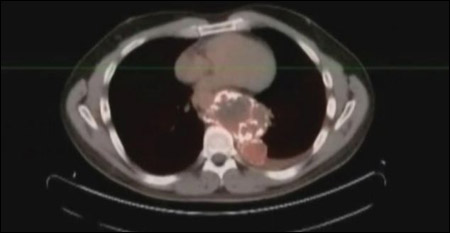

صورة X-Ray للورم السرطاني! |

وقال أبكن "ظننت أنني أشكو من تمزق عضلي لكن الطبيب تجهم ما أن نظر إلى الشاشة التي تكشف ما في داخلي". وأضاف "لم يعرفوا ما الذي ينمو في البداية"، مضيفا انه تبين لاحقا انه ورم صلب بحجم كرة قدم ولديه تشعبات.

وقال الأطباء للرجل أن الورم بات عملاقا وأخذ يضغط على قلبه ورئتيه وأمعائه، وأوضحوا له ان الورم ينمو على ما يبدو منذ قرابة العقد.

وأخضع أبكن لجراحــــة استؤصل فيها الـــورم واضطـــر بعد ذلك للخضـــوع لجراحـــة ترميـــم استغرقت عدة ساعات. وقال د.دي بيرنا ان "محاولة استئصال ورم كبير ومتكلس وصلب كالصخرة كانت تجربة طبية صعبة"، وسيجري أبكن صورا مقطعية مستمرة للتأكد من عدم عودة الورم.